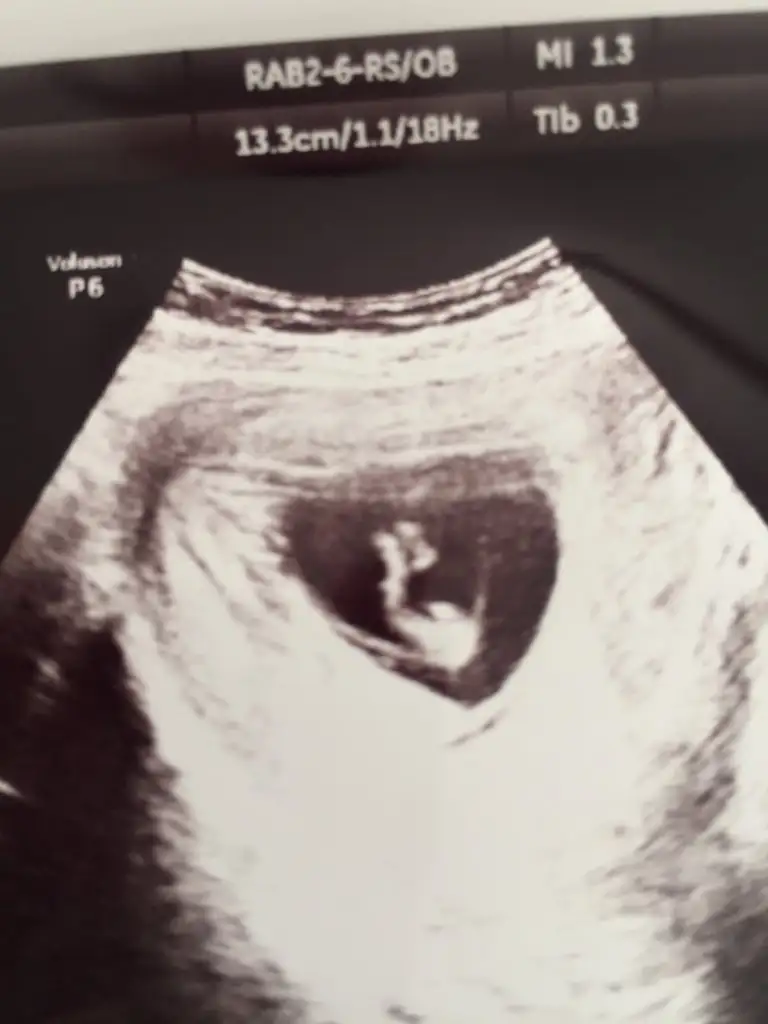

10+1 haftaya göre erkek 11 yada 12 hafta usg tekrar paylaşın çünki 10 haftalarda nub iki tarafa benzerBana da tahmin de buluabilir misiniz?daha küçük ama

Teşekkür ederim yorumladığınız için10+1 haftaya göre erkek 11 yada 12 hafta usg tekrar paylaşın çünki 10 haftalarda nub iki tarafa benzer

10+3 canımKaç haftalık

Erkek diyorum kafa yapısına göre10+3 canım

Erkek gibi geldi banaBenim bebişim bu ultrasonda 11+2 ikinci çocuğum ama bu cinsiyet işinden hiç anlamıyorum. acaba tahmin yapabilir misiniz?

Erkek gibi Canım sağlıkla gelsinmerhaba bugün kontrolüm vardı..

geç döllenmeye göre 10+2 ama usg de 11+2 olarak görünüyor..

bir çok çıktı verdi doktor ve tahminde bulundu..

ama net konuşmak için erken dedi..

ama ben bile anladım cinsiyetini..

sizden de yorum rica ediyorum..

Kız gibiBir tane o da bu biraz daha düzgün çektim